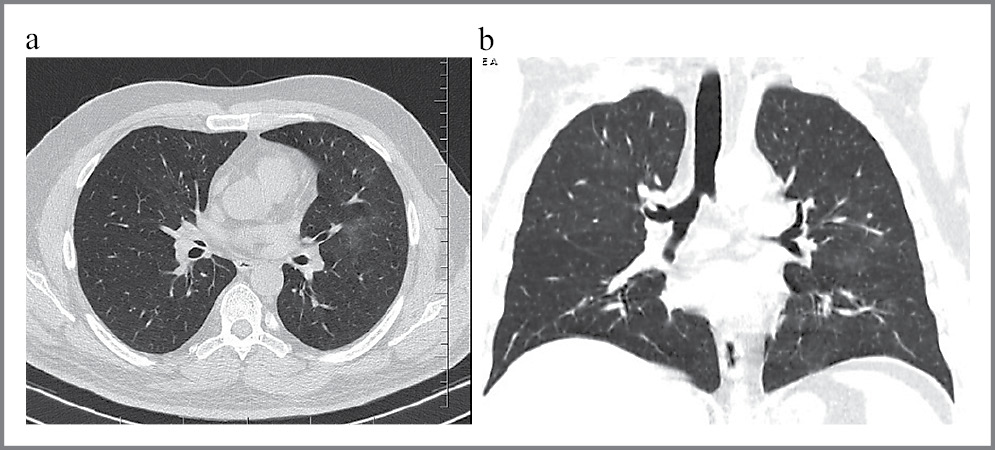

На сегодняшний день «золотым стандартом» диагностики COVID-19 является полимеразная цепная реакция (ПЦР) на выявление РНК вируса с обратной транскрипцией в реальном времени. Данные компьютерной томографии (КТ) у пациентов с первичными ложноотрицательными результатами ПЦР при подозрении на COVID-19 являются существенным дополнением к дифференциальной диагностике (рис. 1) [11, 12].

Рис. 1: а – аксиальная проекция; b – фронтальная проекция. КТ легких у пациента с вирусной пневмонией, вызванной COVID-19. Симптом «матового стекла» и «булыжной мостовой».